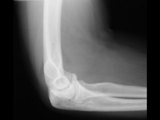

Fat pad sign-posterior-elbow

Fat pad sign-posterior-elbow